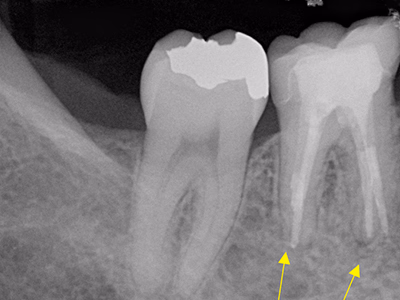

治療前後写真

治療前

治療後

右下奥歯で咬むと違和感がある/歯ぐきが腫れてきた

治療内容

- ① 顕微鏡視下根管治療(マイクロエンド)

- ② 根管拡大・洗浄2回

- ③ 2ヶ月経過観察で再生反応確認後に根管充填

- ④ マイクロスコープ下でファイバーコア築造+セラミック冠装着

サイナストラクトは消失し、CTでも透過像の改善を確認。

術後数日で痛み消失し、セラミック装着後も良好な咀嚼が可能。

現在は年1 回の定期チェックを継続中。